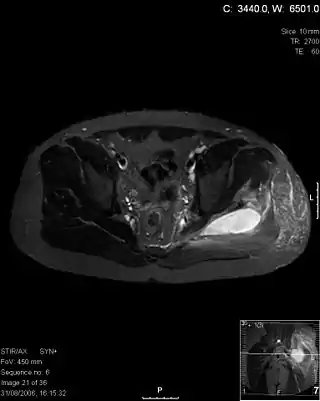

![]() Imagen por resonancia magnética (corte transversal en T2 a nivel de la pelvis) de piomiositis de los músculos glúteo mayor y medio. | ||